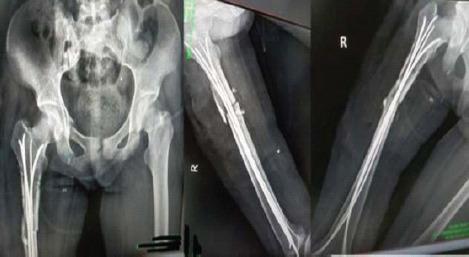

A 25-year-old female patient presented with pain and swelling over the anterolateral aspect of the right thigh after a traumatic road traffic accident 2 days back. On radiological investigation, there was subtrochanteric femur fracture with a butterfly fragment. The patient also had Morel-Lavallee lesion on local ultrasound. Emergency management was done for Morel-Lavallee lesion in the form of percutaneous drainage and compression bandage; fixation was done in the form of external fixator. The wound progressed into complete skin necrosis so external fixator was removed and thorough wound debridement was done. Fracture stabilized with four TENS nails (titanium elastic nail). Removal of the TENS nail and exchange nailing in the form of intramedullary interlocking nail was performed after complete soft-tissue healing. Bony union seen at the fracture site clinically and radiologically at 3-month follow-up.

一名25岁女性患者在2天前发生道路交通事故后,出现右大腿前外侧疼痛和肿胀。经影像学检查,发现股骨转子下骨折并伴有蝶形骨块。患者在局部超声检查中还发现有莫雷尔-拉瓦利损伤。对莫雷尔-拉瓦利损伤进行了急诊处理,采用经皮引流和加压包扎;以外部固定器的形式进行固定。伤口发展为完全皮肤坏死,因此拆除了外部固定器并进行了彻底的伤口清创。用四根TENS钉(钛弹性钉)使骨折稳定。在软组织完全愈合后,取出TENS钉并以髓内交锁钉的形式进行更换钉。在3个月的随访中,骨折部位在临床和影像学上均可见骨愈合。